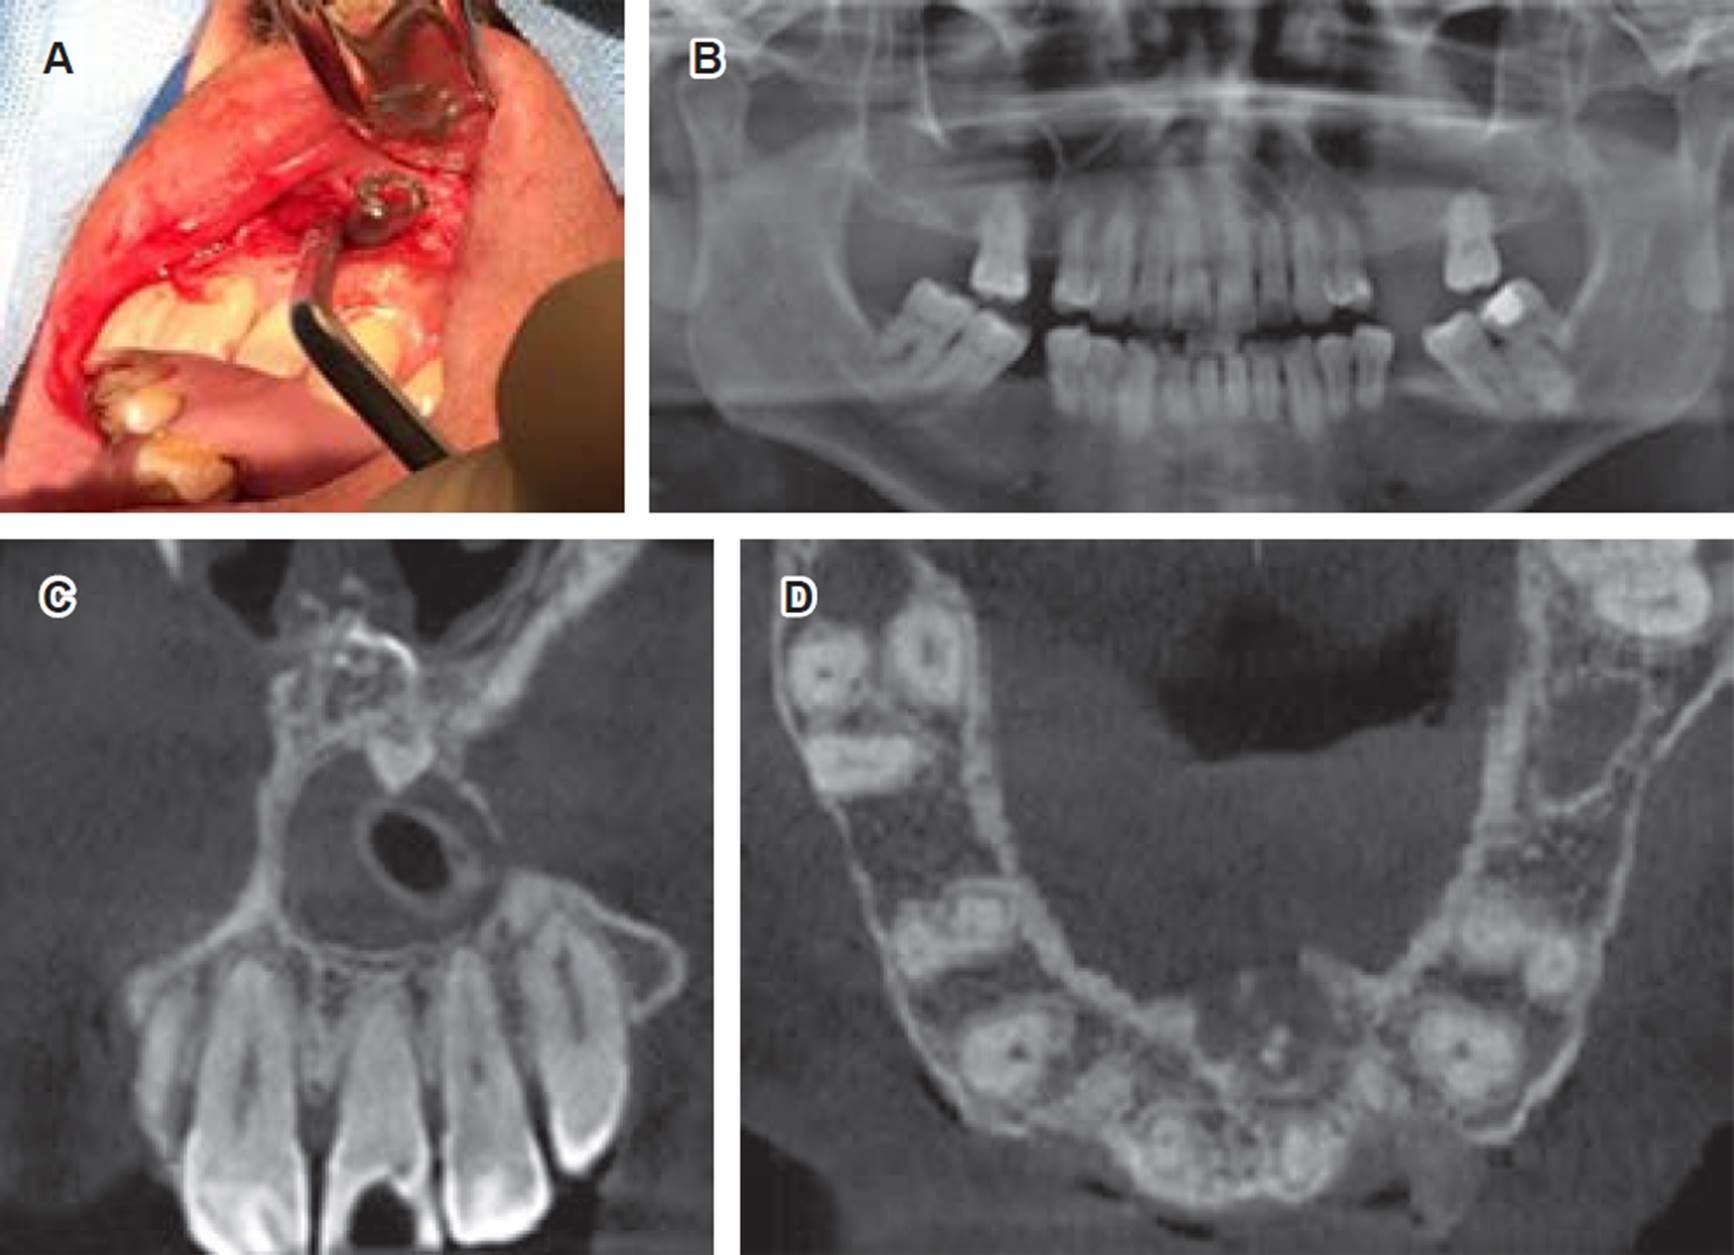

Paciente de género masculino de 43 años de edad consulta por aumento de volumen en paladar. Sin antecedentes sistémicos, relata dolor moderado, intermitente, localizado junto a sensación opresiva en sector anterosuperior maxilar, con tiempo de evolución desconocido. Al examen clínico se observa tumoración en fondo de vestíbulo y paladar, extendida desde 2.2 hasta 1.1, de forma redondeada, consistencia firme, cubierta por mucosa normal, doloroso a la palpación y de límites definidos. Los dientes involucrados presentaban caries, pero se encontraban vitales a las pruebas endodónticas y no presentaban movilidad ni desplazamiento (Figura 1A).

Figura 1 A) Imagen intraoral clínica de lesión a nivel de paladar duro. Se observa tumoración redondeada, no ulcerada y mucosa de coloración normal en la parte anterior del maxilar relacionada con los incisivos anterosuperiores. B) Examen imagenológico CBCT corte sagital; se observa lesión quística que genera expansión de corticales vestibular y palatina, asociada a mesiodens invertido, proyectado en cavidad nasal.

En una primera instancia, se observó radiográficamente presencia de lesión radiolúcida de gran tamaño. Sin embargo, se observó integridad de espacios periodontales en los dientes comprometidos, por lo que se solicitó complementar con ortopantomografía y CBCT, donde se encontró una lesión osteolítica circunscrita, bien delimitada con márgenes corticalizados en relación con raíces dentarias de dientes 1.1 a 2.2, confirmando la presencia de lesión quística en zona maxilar anterosuperior asociada a la existencia de diente supernumerario invertido de localización buconasal con la corona proyectada hacia la cavidad nasal y la raíz orientada a la cavidad oral, con diámetros de 2.5 × 2.0 × 1.9 cm. Se evidenció además expansión de corticales óseas vestibular y palatina, generando un desplazamiento del conducto nasopalatino, sin compromiso de raíces de dientes vecinos (Figura 1B).

Posterior a consentimiento informado, se realiza biopsia incisional bajo anestesia local, donde se procede a instalar una cánula de descompresión con el objetivo de disminuir el tamaño de la lesión y se indicó aseo con clorhexidina al 0.12% tres veces al día con seguimiento radiográfico a los seis meses (Figura 2A). Con hipótesis diagnóstica de tumor odontogénico adenomatoide, las muestras obtenidas fueron enviadas a estudio histopatológico, el cual mostró una membrana quística con revestimiento epitelial escamoso no queratinizado, de pocas capas, focos de calcificaciones distróficas siendo características sugestivas de quiste dentígero. Tras seis meses de la intervención se realizó una nueva evaluación clínica e imagenológica, donde el paciente relató disminución del tamaño de la lesión y cese de sintomatología opresiva en relación con el sector anatómico comprometido, observándose radiográficamente una disminución del tamaño de la lesión quística en sec tor anterosuperior con un diámetro de 1.4 × 1.7 × 1.5 cm asociada a la presencia de cánula de descompresión en su espesor (Figura 2B-D).

Figura 2 A) Biopsia incisional de lesión quística. Se observa instalación de cánula de descompresión e irrigación. B-D) Exámenes imagenológicos de control a los seis meses posterior a descompresión. B) Ortopantomografía; se observa lesión radiolúcida a nivel anterosuperior con cánula de descompresión. C) CBCT corte coronal, se observa lesión quística con cánula en su espesor y mesiodens invertido el cual se proyecta entre cavidad oral y nasal. D) CBCT corte transversal, se evidencia conducto nasopalatino desplazado por lesión quística y aumento de volumen palatino.